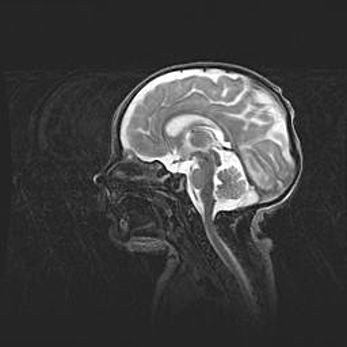

Мальформация Денди-Уокера. Киста задней черепной ямки.

Агенезия мозолистого тела.

Возраст: 2,5 месяца

Вес: 2420 г

Пол: женский

Окружность головы: 37 см

Срок гестации: 32 недели

Мальформация Денди—Уокера — редкий вид патологии ЦНС, представляющий собой врожденный порок развития каудального отдела ствола и червя мозжечка, ведущий к неполному раскрытию срединной (Мажанди) и латеральных (Лушка) апертур IV желудочка мозга. Для этогно синдрома характерна триада симптомов: гипотрофия червя мозжечка и/или полушарий мозжечка, кисты задней черепной ямки, гидроцефалия различной степени. В 70% случаев порок сочетается и с другими аномалиями головного мозга, в частности с агенезией мозолистого тела.